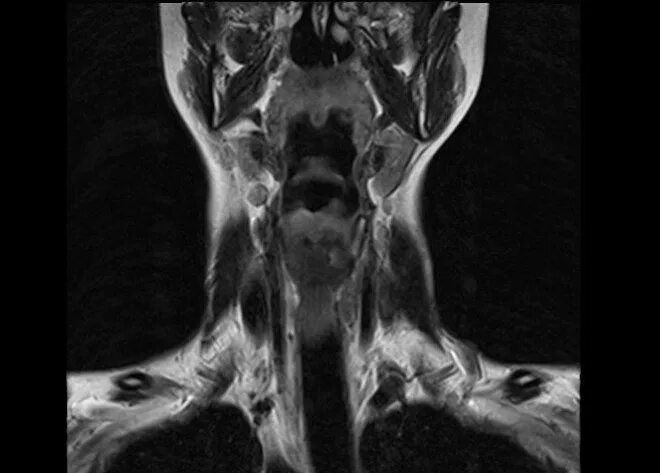

Кт тканей